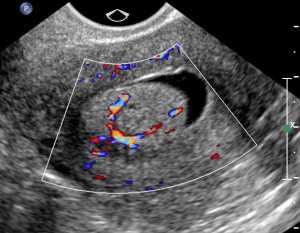

Допплерография

Такой метод УЗИ позволяет оценить кровоток в репродуктивных органах и выявить причины его нарушения. Это обязательная процедура в период планирования беременности, особенно при наличии у женщины тяжелых системных болезней, гестоза (в анамнезе), патологии почек.

В процессе исследования используется:

- дуплексное сканирование с целью определения размеров артерий и вен, направления кровотока, а также пропускной способности исследуемых сосудов;

- цветовое или триплексное сканирование для оценки скорости и направления сосудов.

Оно характеризуется наличием разных цветов.

В современных аппаратах УЗИ система допплерографии уже встроена, поэтому эти исследования часто комбинируются.